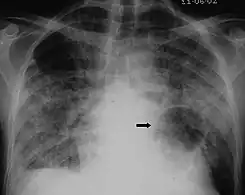

X-ray of a cyst in pneumocystis pneumonia[7]

The diagnosis can be confirmed by the characteristic appearance of the chest X-ray and an arterial oxygen level (PaO2) that is strikingly lower than would be expected from symptoms. Gallium 67 scans are also useful in the diagnosis. They are abnormal in about 90% of cases and are often positive before the chest X-ray becomes abnormal. Chest X-ray typically shows widespread pulmonary infiltrates. CT scan may show pulmonary cysts (not to be confused with the cyst-forms of the pathogen).